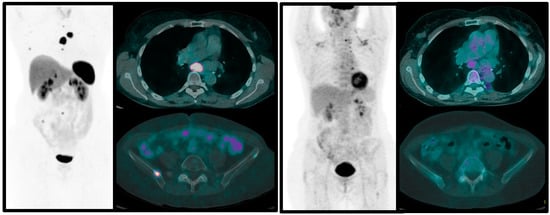

- Zidan, L.; Iravani, A.; Kong, G.; Akhurst, T.; Michael, M.; Hicks, R.J. Theranostic implications of molecular imaging phenotype of well-differentiated pulmonary carcinoid based on 68Ga-DOTATATE PET/CT and 18F-FDG PET/CT. Eur. J. Nucl. Med. Mol. Imaging 2021, 48, 204–216. [Google Scholar] [CrossRef]

- Albano, D.; Dondi, F.; Bauckneht, M.; Albertelli, M.; Durmo, R.; Filice, A.; Versari, A.; Morbelli, S.; Berruti, A.; Bertagna, F. The diagnostic and prognostic role of combined [18F]FDG and [68Ga]-DOTA-peptides PET/CT in primary pulmonary carcinoids: A multicentric experience. Eur. Radiol. 2022, 33, 1–11. [Google Scholar] [CrossRef] [PubMed]